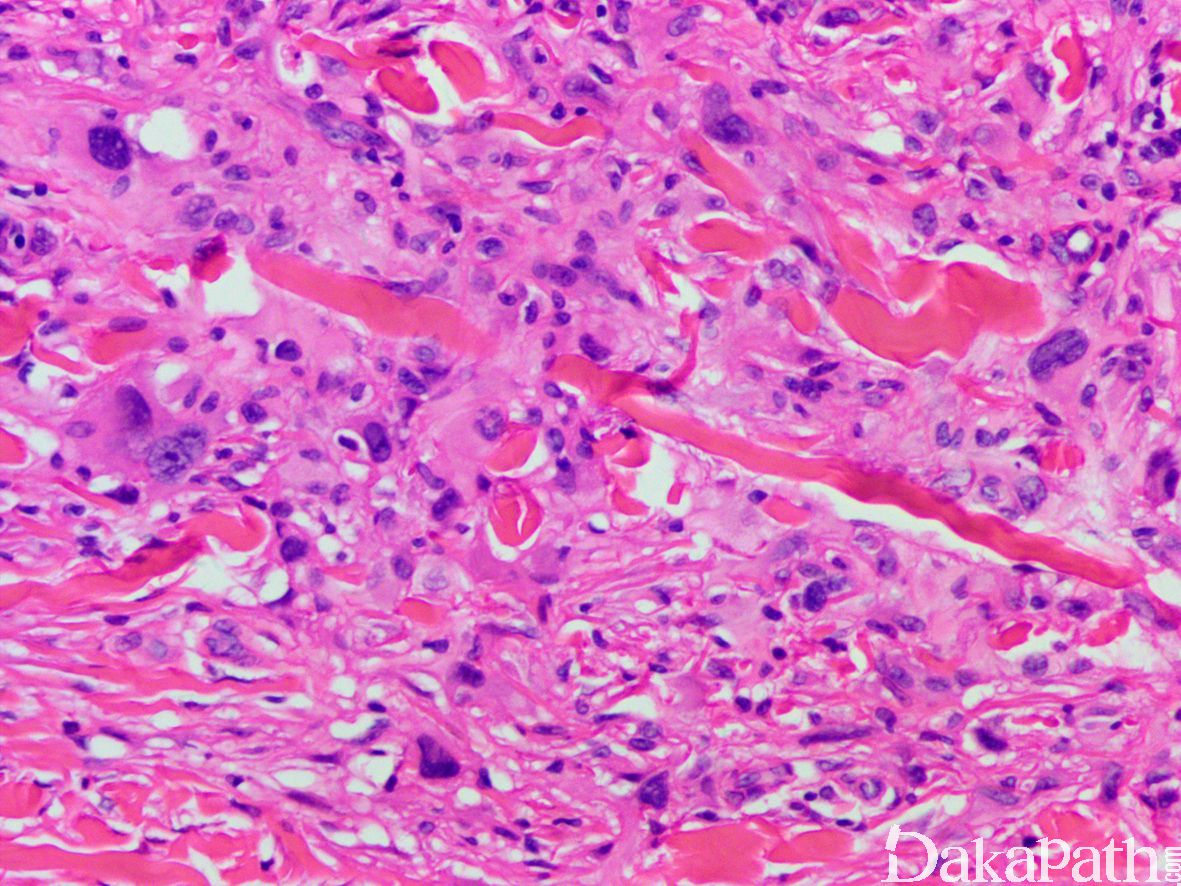

病变主要位于真皮层,偶尔累及皮下脂肪;组织学上表现为经典的纤维组织细胞瘤背景中(梭形细胞席纹状排列,周围可见内陷的厚的胶原纤维)的多形性瘤细胞;

多形性瘤细胞可见多少不等的核大深染、核形规则的多形性细胞或畸形细胞,胞质嗜伊红色或泡沫样,有时可含有含铁血黄素,核分裂多少不等(1-15 个/10HPF),多数比较少见,偶尔可见非典型核分裂象和坏死;

多数病例可见多核巨细胞,有些类似于杜顿巨细胞。